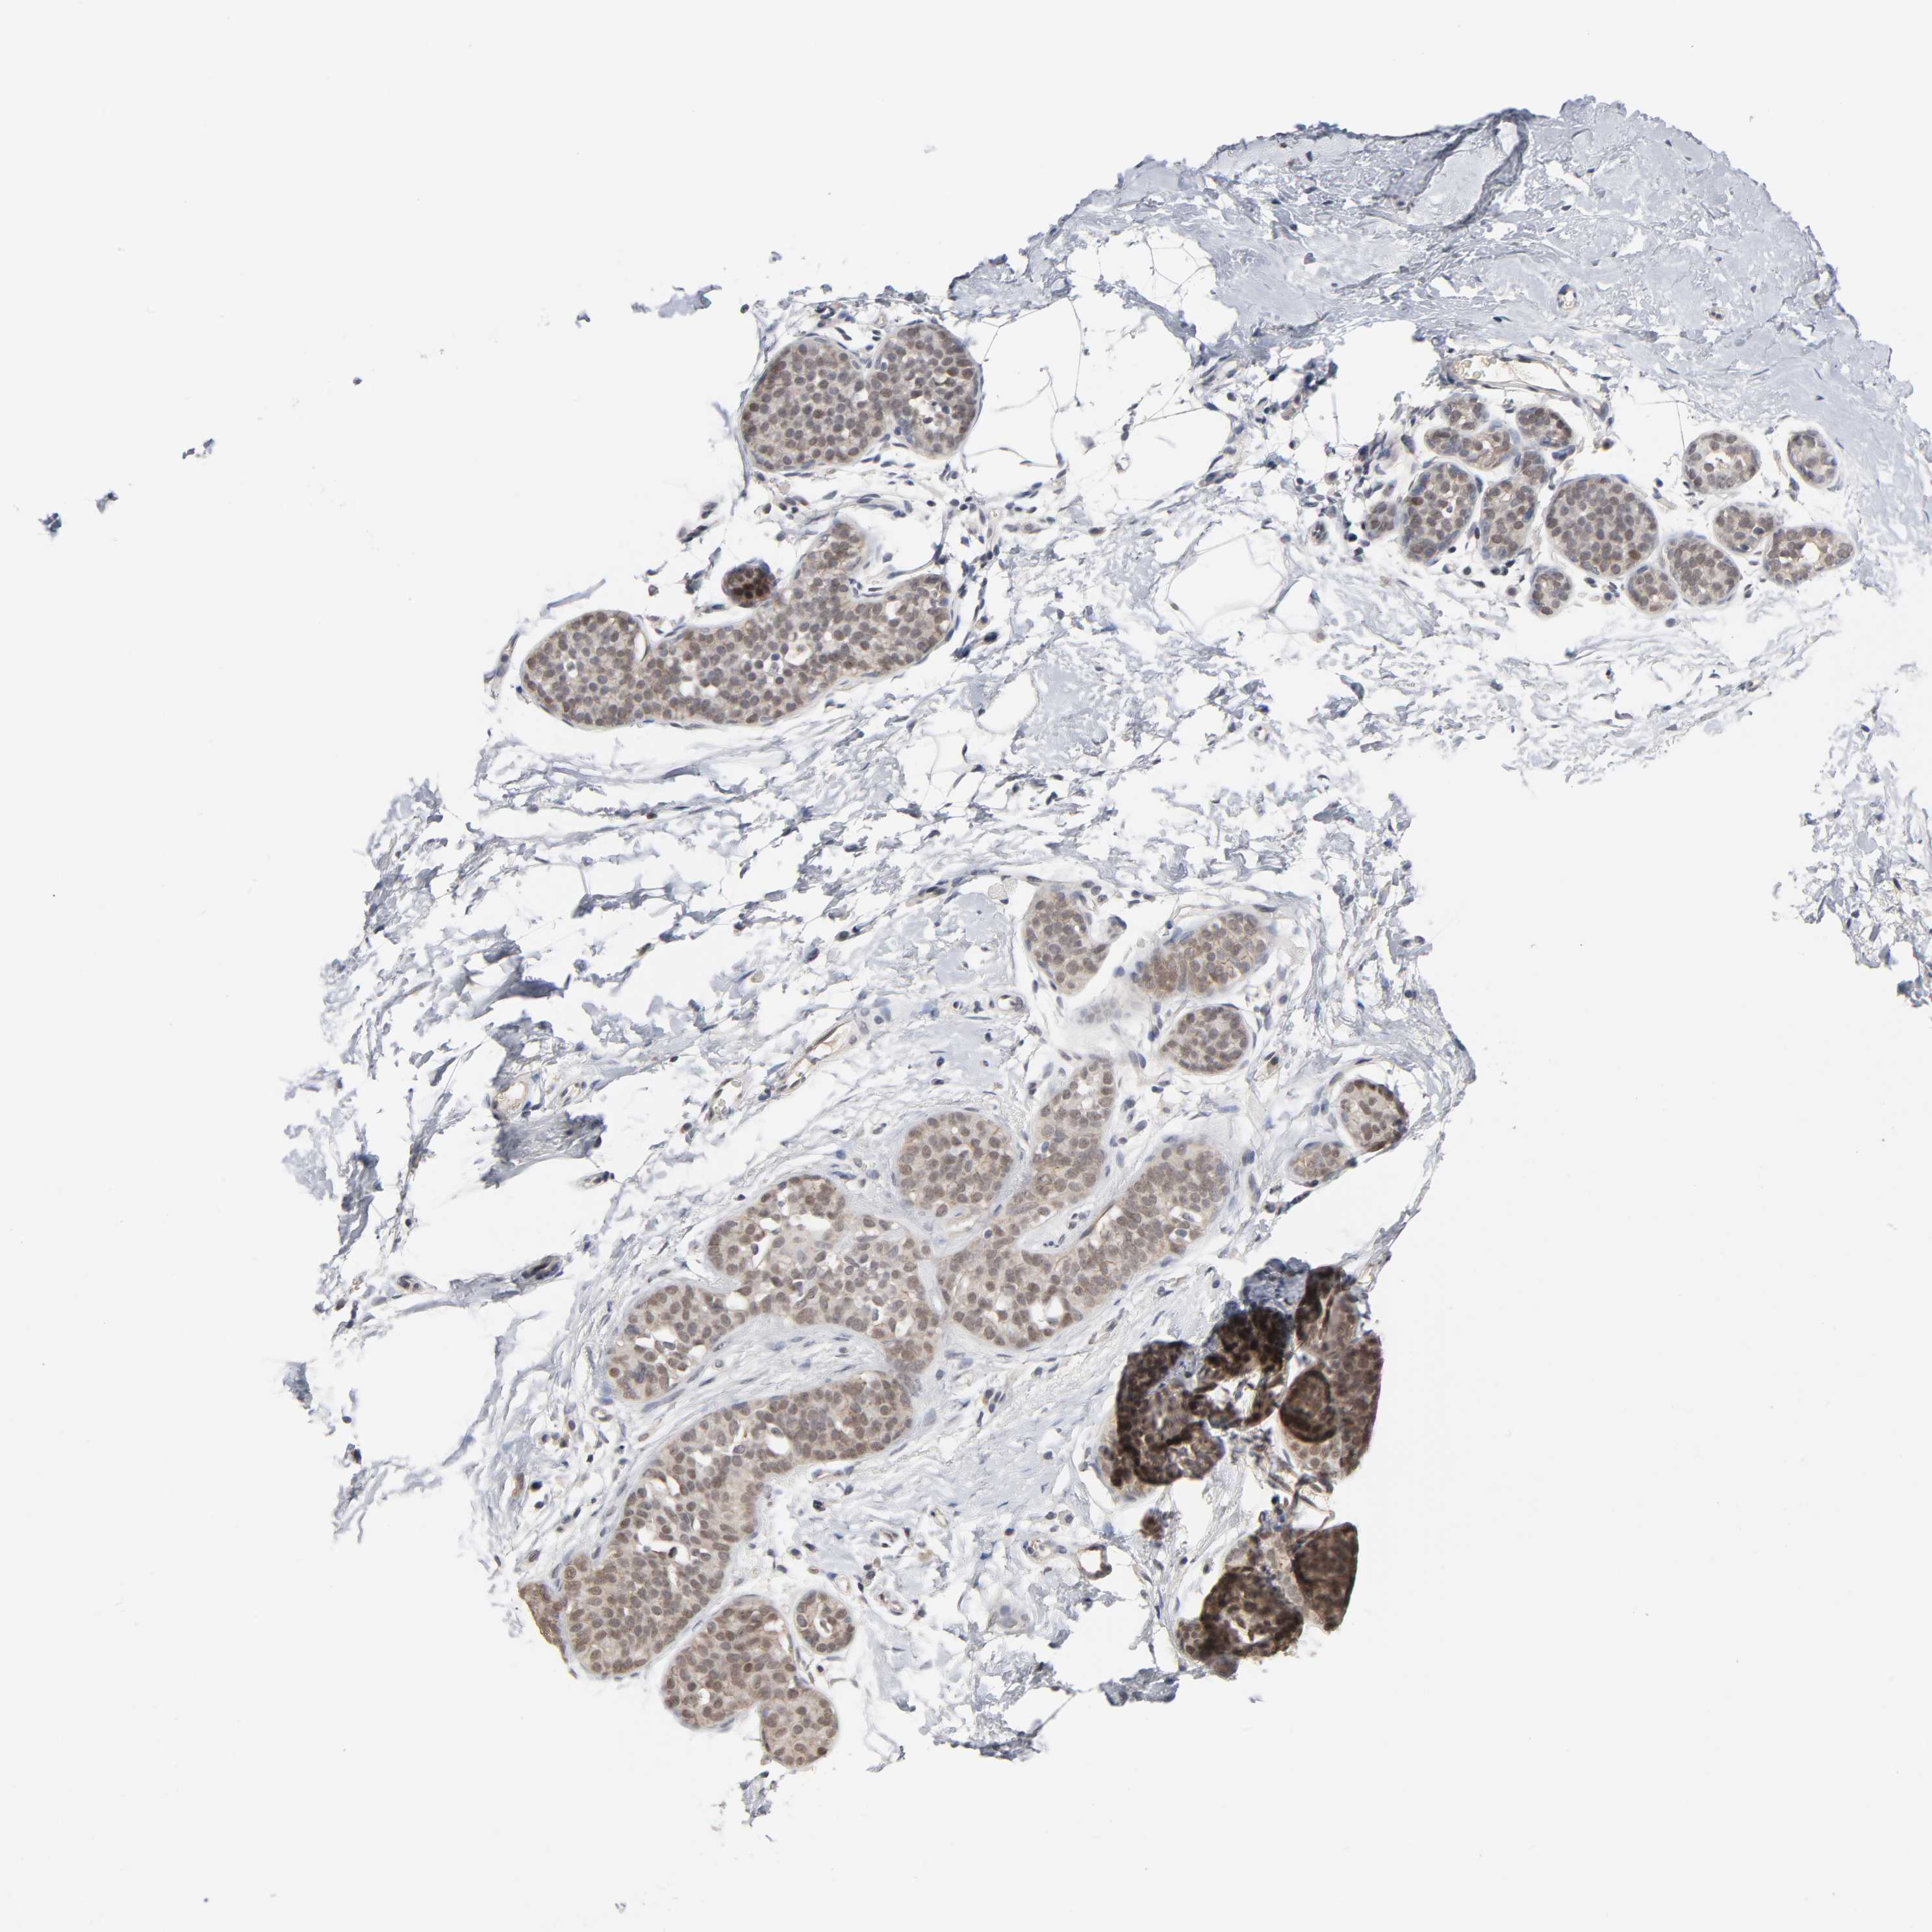

CANCER BREAST CANCER Show tissue menu

BRCA TCGA BRCA VALIDATION PROTEIN EXPRESSION